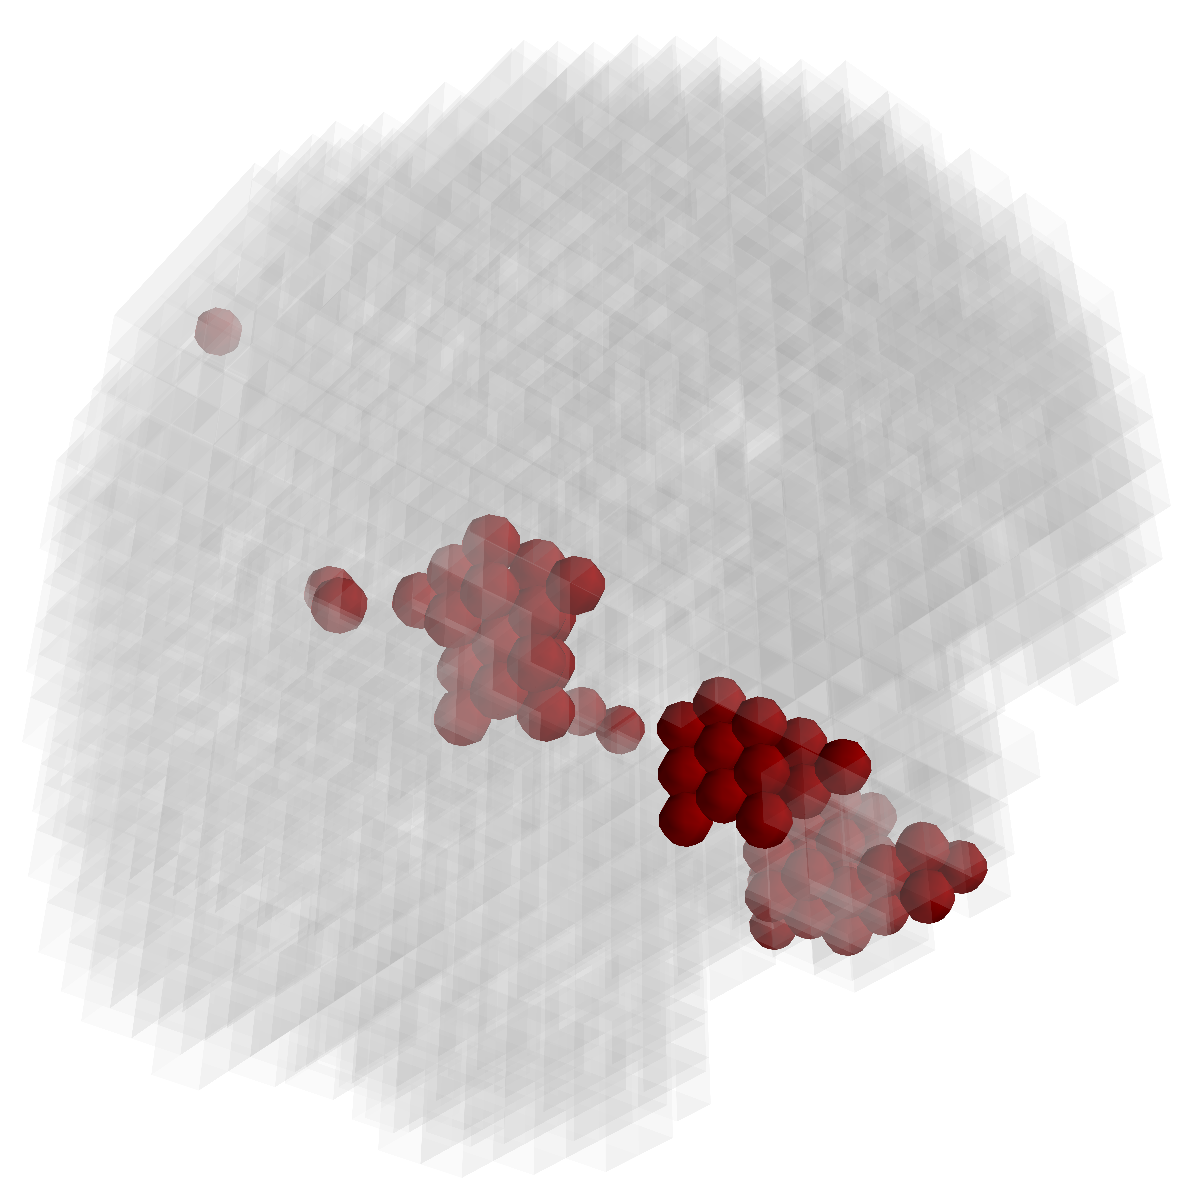

Figure 2: Feature selection by different models. The top row illustrates selected voxels in a 3D model (voxels with positive β𝛽\beta are in brown and negative ones are in blue), the mid and bottom rows illustrate the corresponding projections on brain slices.

Feature selection. For each task, the selected features are those whose β𝛽\beta are not zero . In Figure 2, the result of 30ADNC is used to illustrate the feature selection by different models (using the parameters at their best accuracy). As shown, the selected voxels by both GFL and n2superscript𝑛2n^{2}GFL cluster into several spatially connected regions, whereas those of lasso and T-test/MLDA scatter around. Also, as mentioned before, the LapL tends to select much more voxels than necessary due to the l2subscript𝑙2l_{2} regularization. Moreover, the selected voxels by GFL and n2superscript𝑛2n^{2}GFL are concentrated in Hippocampus, ParaHippocampal gyrus (which are believed to be the early damaged regions). On the other hand, the lasso and T-test/MLDA either select less lesion voxels or select probably noisy voxels not in the early damaged regions.